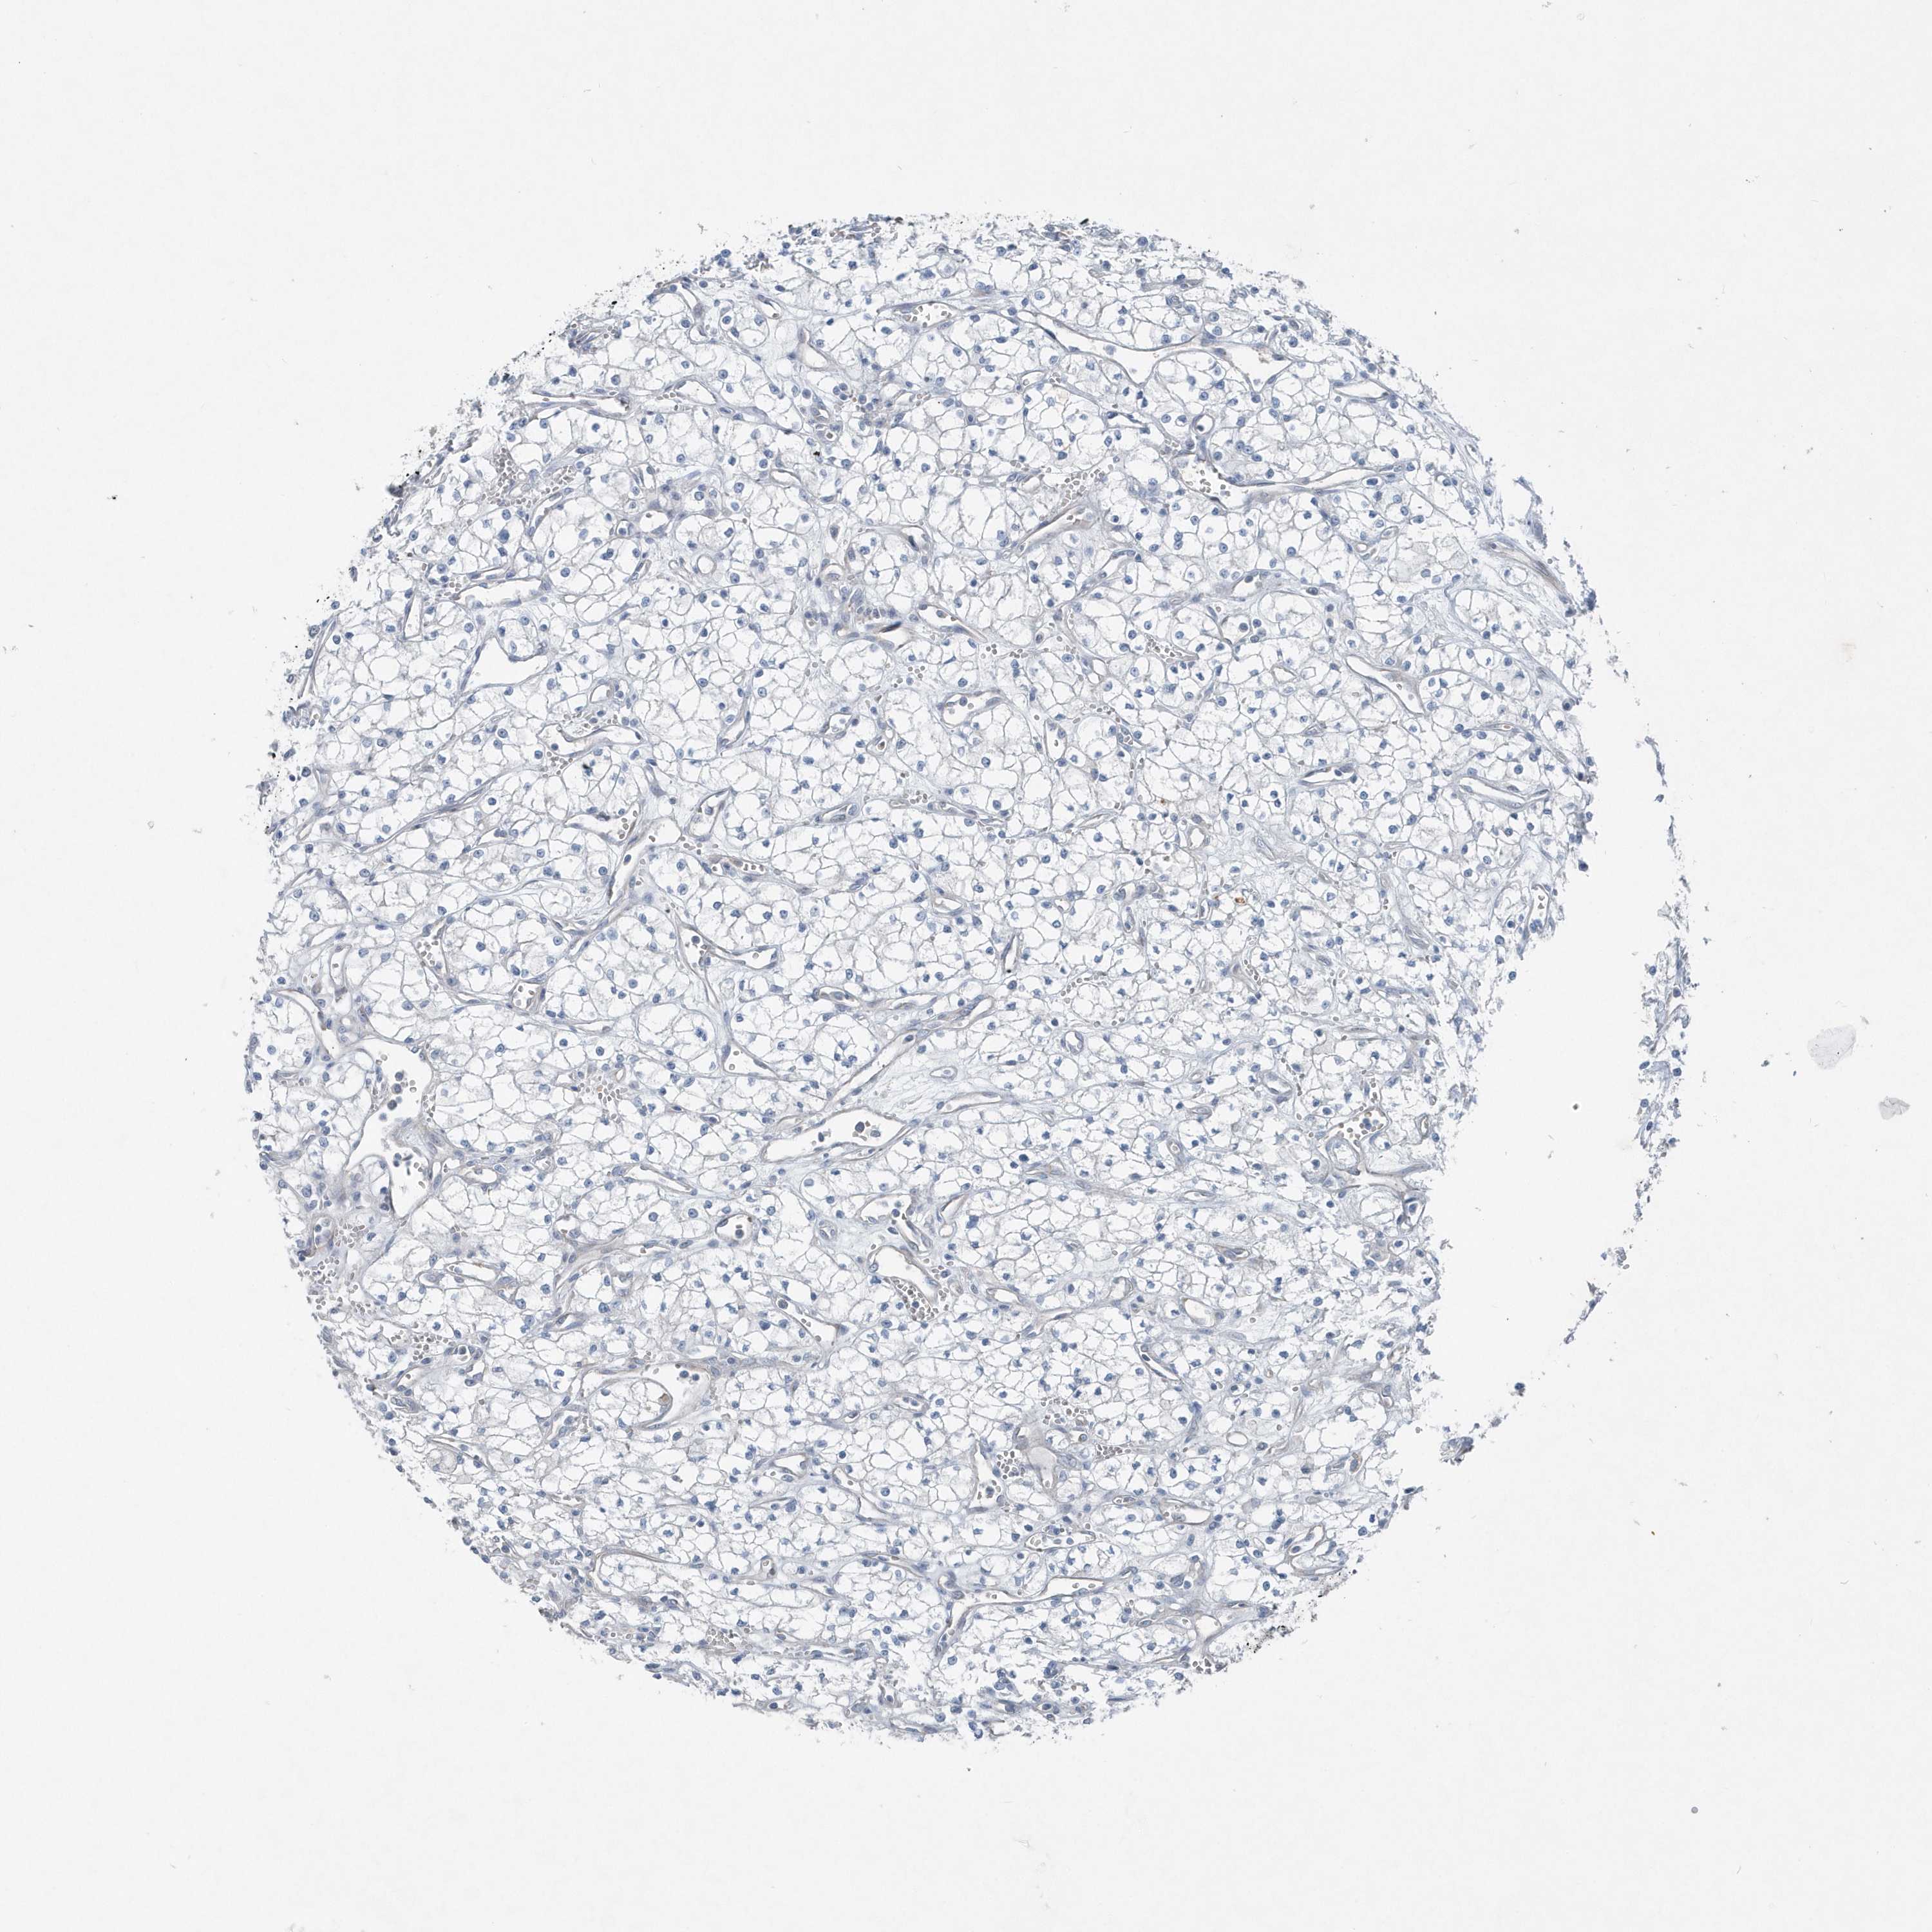

KIDNEY RENAL CLEAR CELL CARCINOMA (TCGA) - Interactive survival scatter ploti

The Survival Scatter plot shows the clinical status (i.e. dead or alive) for all individuals in the patient cohort, based on the same data that underlies the corresponding Kaplan-Meier plots. Patients that are alive at last time for follow-up are shown in blue and patients who have died during the study are shown in red.

The x-axis shows the expression levels (FPKM) of the investigated gene in the tumor tissue at the time of diagnosis. The y-axis shows the follow-up time after diagnosis (years). Both axes are complimented with kernel density curves demonstrating the data density over the axes. The top density plot shows the expression levels (FPKM) distribution among dead (red) and alive patients (blue). The right density plot shows the data density of the survived years of dead patients with high and low expression levels respectively, stratified using the cutoff indicated by the vertical dashed line through the Survival Scatter plot. This cutoff is automatically defined based on the FPKM cutoff that minimizes the p-score. The cutoff can be changed by dragging the vertical line or by entering a cutoff value in the square labeled "Current cut-off".

Under the Survival Scatter plot the p-score landscape (black curve; left axis) is shown together with dead median separation (red curve; right axis). Dead median separation is the difference in median mRNA expression between patients who have died with high and low expression, respectively. It is calculated as follows: median FPKM expression of dead patients with high expression - median FPKM expression of dead patients with low expression. This is intended to aid the user in visually exploring custom cutoffs and the associated p-scores and dead median separation.

Individual patient data is displayed and can be filtered by clicking on one or more of the category buttons on the top of the page. Categories describing expression level and patient information include: high, low, alive, dead, female, male and tumor stages. The scale of the x-axis can be toggled between linear and log-scale by clicking on the "x log" button. Mouse-over function shows TCGA ID, patient information and mRNA expression (FPKM) for each patient.

& Survival analysisi

Kaplan-Meier plots summarize results from analysis of correlation between mRNA expression level and patient survival. Patients were divided based on level of expression into one of the two groups "low" (under cut off) or "high" (over cut off). X-axis shows time for survival (years) and y-axis shows the probability of survival, where 1.0 corresponds to 100 percent.

MCC is validated prognostic, high expression is favorable in Kidney Renal Clear Cell Carcinoma (TCGA)

Best expression cut offi

Based on the FPKM value of each gene, patients were classified into two groups and association between prognosis (survival) and gene expression (FPKM) was examined. The best expression cut-off refers the FPKM value that yields maximal difference with regard to survival between the two groups at the lowest log-rank P-value. Best expression cut-off was selected based on survival analysis .

When clicking on this number, the vertical dashed line indicating cut-off, the interactive survival plot, and the Kaplan-Meier curve will be adjusted to show results based on the best expression cut-off.

: 6.25

TCGA RNA samplesi

RNA-seq data is reported as average FPKM (number Fragments Per Kilobase of exon per Million reads), generated by the The Cancer Genome Atlas (TCGA) .

Normal distribution across the dataset is visualized with box plots, shown as median and 25th and 75th percentiles. Points are displayed as outliers if they are above or below 1.5 times the interquartile range. FPKM values of the individual samples are presented next to the box plot.

Average pTPM 5.7

Number of samples 521